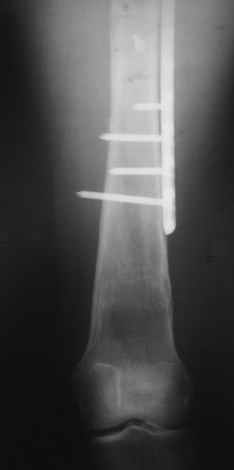

Пациентка 23 лет, доставлена в клинику с Диагнозом: Закрытый сегментарный оскольчатый перелом левой бедренной кости в верхней и средней трети. Травма в результате ДТП 10.03.2006г. Из анамнеза у пациентки диспластический левосторонний коксартроз, S-образный сколиоз 2ст. В 1999г в Кургане выполнялась остеотомия бедра в нижней трети и коррекция укорочения конечности на 3 см (рентгенограммы бедра и таза до травмы в приложении). До получения травмы пациентка ходила без боли с полной нагрузкой на левую ногу. Учитывая дисплазию левого ТБС, пациентке, вероятно, предстоит операция тотального эндопротезирования лев ТБС, что требует анатомичного восстановления проксимальногоотдела бедра. Рассматриваются следующие вариант остеосинтеза:1) Экстракортикальный остеосинтез проксимального и дистального перелома пластиной с угловой стабильностью типа LISS( г Рыбинск); 2) Ретроградный интрамедуллярный блокированный остеосинтез дистального перелома и накостный синтез проксимального пластиной с угловойстабильностью; 3) Остеосинтез бедра в аппарате внешней фиксации с фиксацией таза и возможной открытой адаптацией фрагментов. Хотелось бы узнать Ваше мнение. С уважением Украинский Евгений, г.Краснодар, ККБ N1, ТОО N3.

Уважаемые коллеги, приношу извенения за молчание. Готовили материал и боялись писать раньше времени. Все хотели убедиться в том, что после операции все будет спокойно. Спасибо за отклики и советы. К сожалению, гамма-гвоздя, штифтов с возможностью установки более 2-х блокирующих винтов у нас нет. Зато нашли достаточно длинную пластину с угловой стабильностью. После проведения предоперационной подготовки и планирования выполнили остеосинтез. В условиях рентгеноперационной, после репозиции дистрактором из одного разреза 5см в проксимальном отделе подкожно установили пластину. Пришлось выполнить дополнительный разрез до5см в проекции перелома диафиза в средней трети, из которого удалось репонировать перелом и выполнить фиксацию стягивающим винтом. Затем все завершилось наложением пластины с угловой стабильностью. Пластина оказалась достаточно длинной, что позволило перекрыть все переломы с фиксацией каждого отломка минимум 5-ю винтами. Синтез достаточно стабилен. Пациентка активизирована на 3-и сутки(снимки прилагаются). В настоящий момент пациентка выписана на амбулаторное лечение. Еще раз, огромное спасибо всем за помощь в выборе тактики и просто совете. С уважением Украинский Е.

Прошу прощения, со снимками глюк произошел. Высылаю. С уважением Евгений У.